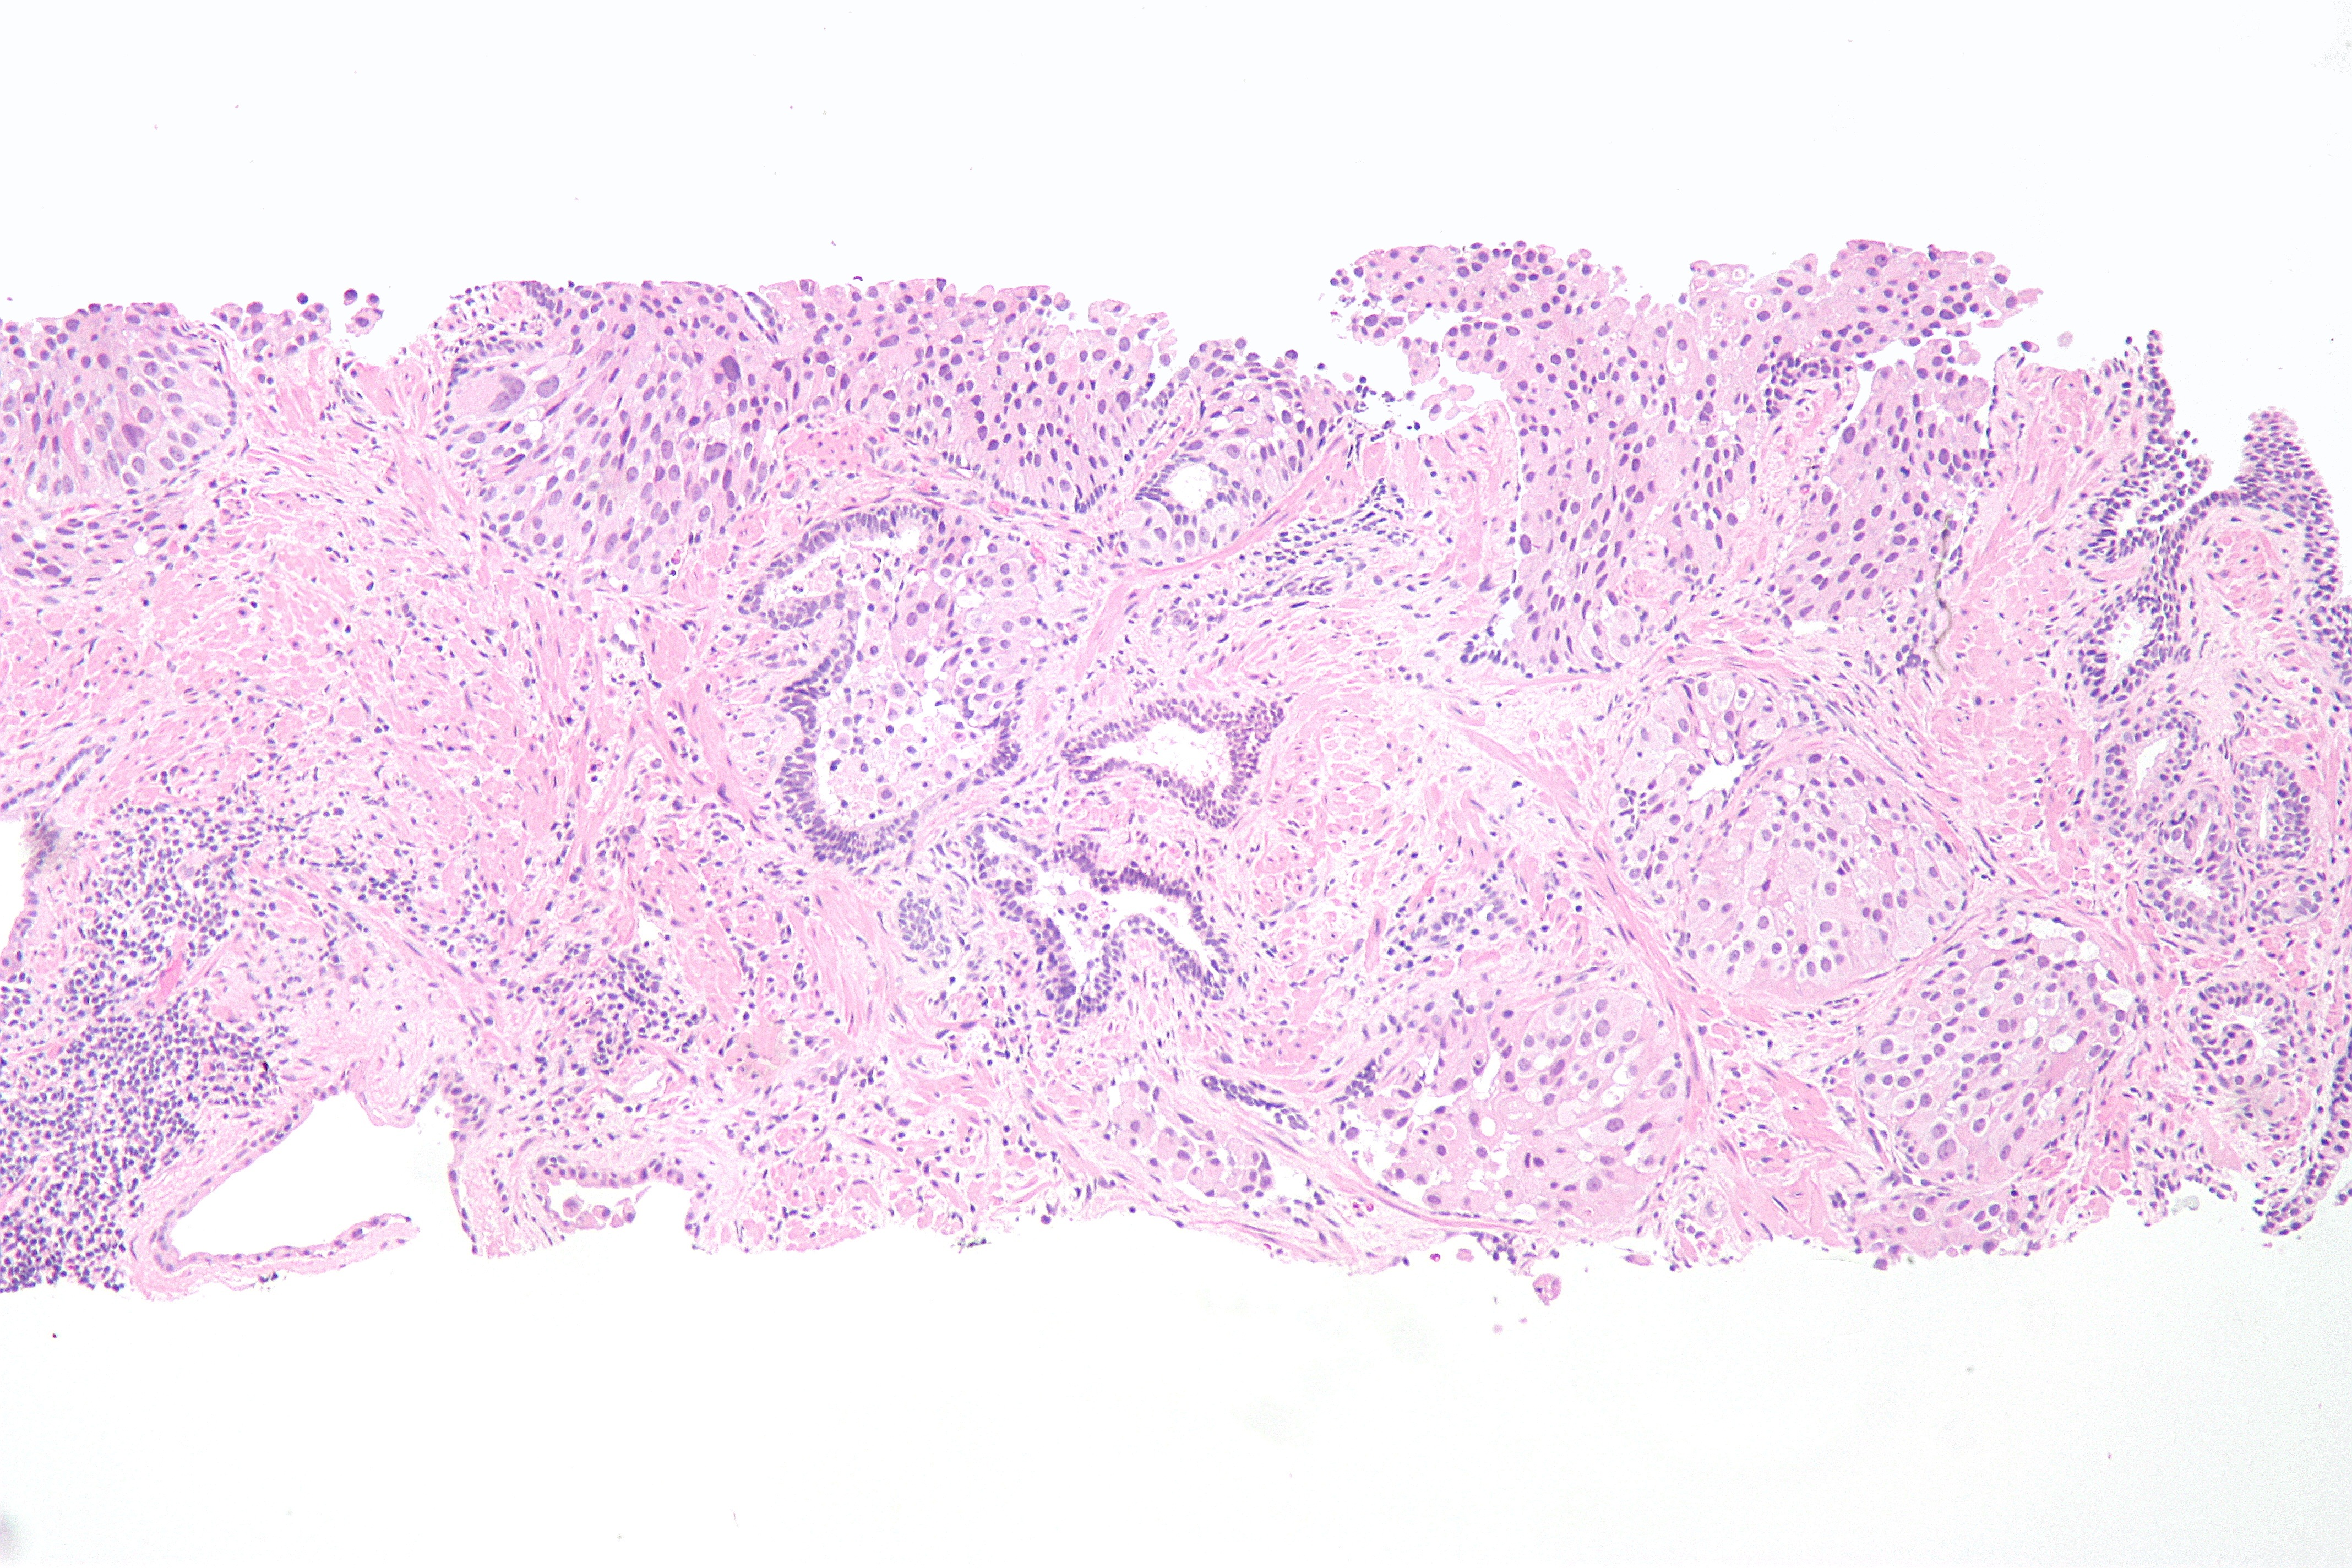

이행상피세포암종은 주로 유두상(70%)과 비유두상(30%)으로 나뉜다.[2]

1973년 WHO의 이행상피세포암종 분류 체계(유두종, G1, G2, G3)가 가장 일반적으로 사용되었으나, 2004년 WHO[13]의 유두상 유형 분류(낮은 악성 잠재력의 유두상 신생물(PNLMP), 저등급 및 고등급 유두상 암종)로 대체되었다. 고등급 암종은 일반적으로 더 많은 다형성, 다수의 유사분열, 진염색질 및 비교적 두드러진 인, 그리고 불균일한 핵 분포를 보인다.